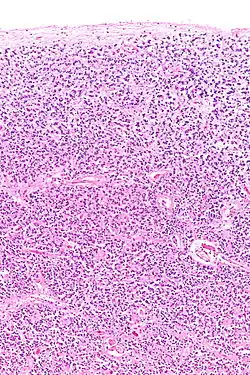

The pineal body in humans consists of a lobular parenchyma of pinealocytes surrounded by connective tissue spaces. The gland's surface is covered by a pial capsule.

The pineal gland consists mainly of pinealocytes, but four other cell types have been identified. As it is quite cellular (in relation to the cortex and white matter), it may be mistaken for a neoplasm.[18]

| Pinealocytes | The pinealocytes consist of a cell body with 4–6 processes emerging. They produce and secrete melatonin. The pinealocytes can be stained by special silver impregnation methods. Their cytoplasm is lightly basophilic. With special stains, pinealocytes exhibit lengthy, branched cytoplasmic processes that extend to the connective septa and its blood vessels. |

| Interstitial cells | Interstitial cells are located between the pinealocytes. They have elongated nuclei and a cytoplasm that is stained darker than that of the pinealocytes. |

| Perivascular phagocyte | Many capillaries are present in the gland, and perivascular phagocytes are located close to these blood vessels. The perivascular phagocytes are antigen presenting cells. |

| Pineal neurons | In higher vertebrates neurons are usually located in the pineal gland. However, this is not the case in rodents. |

| Peptidergic neuron-like cells | In some species, neuronal-like peptidergic cells are present. These cells might have a paracrine regulatory function. |